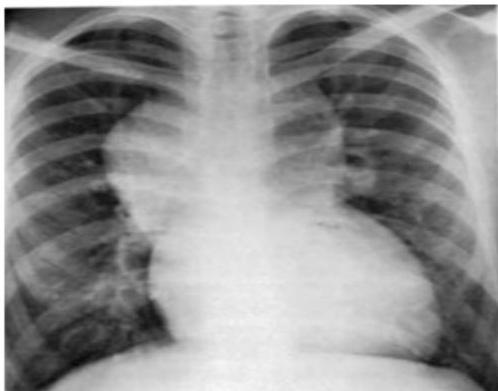

Asthma with Pneumothorax / Emphysema (CXR)

in This PIC Be Curfiat → Check Countage of the lung

Hint: Loss of contour of lung

- Check if hyperinflated

The hint is loss of Couture of lung in the emphysema → we doubt see?

Scenario: 5 year old with 3 days of acute asthma, progressive SOB, cyanosis.

CXR findings?

- Right-sided pneumothorax (or horizontal pneumothorax), subcutaneous emphysema, with left mediastinal shift

- Loss of lung opacity

- Mucous plug causing collapse/obstruction

- Other mentions in original: “Liver & mucus”, “Pneumonitis”

Examination Findings (Chest):

- Hyperresonance (increased sound on percussion)

- Pulsus paradoxus

- Decreased breath sounds

Management?

- Address the underlying cause (e.g., decompression for pneumothorax, airway clearance)

- Bronchodilator, inhaled steroid

- Suction + physiotherapy

- If pneumothorax: chest tube — 5th intercostal space, anterior axillary line

- Possible intubation